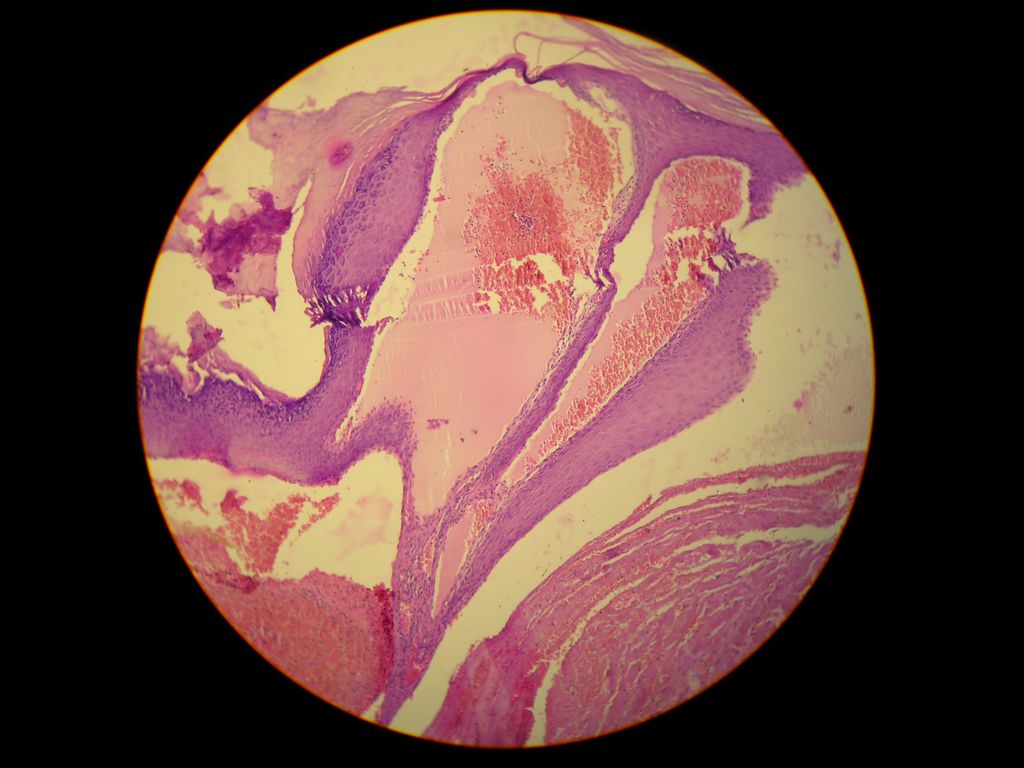

Histopatologia: hiperqueratosis compacta, hipergranulosis y acantosis irregular, presencia de espacios capilares dilatados con numerosos eritrocitos en dermis papilar, alternando con espaciosos dilatados, de paredes delgadas llenos de linfa, no hay infiltrado inflamatorio; compatible con ANGIOQUERATOMA